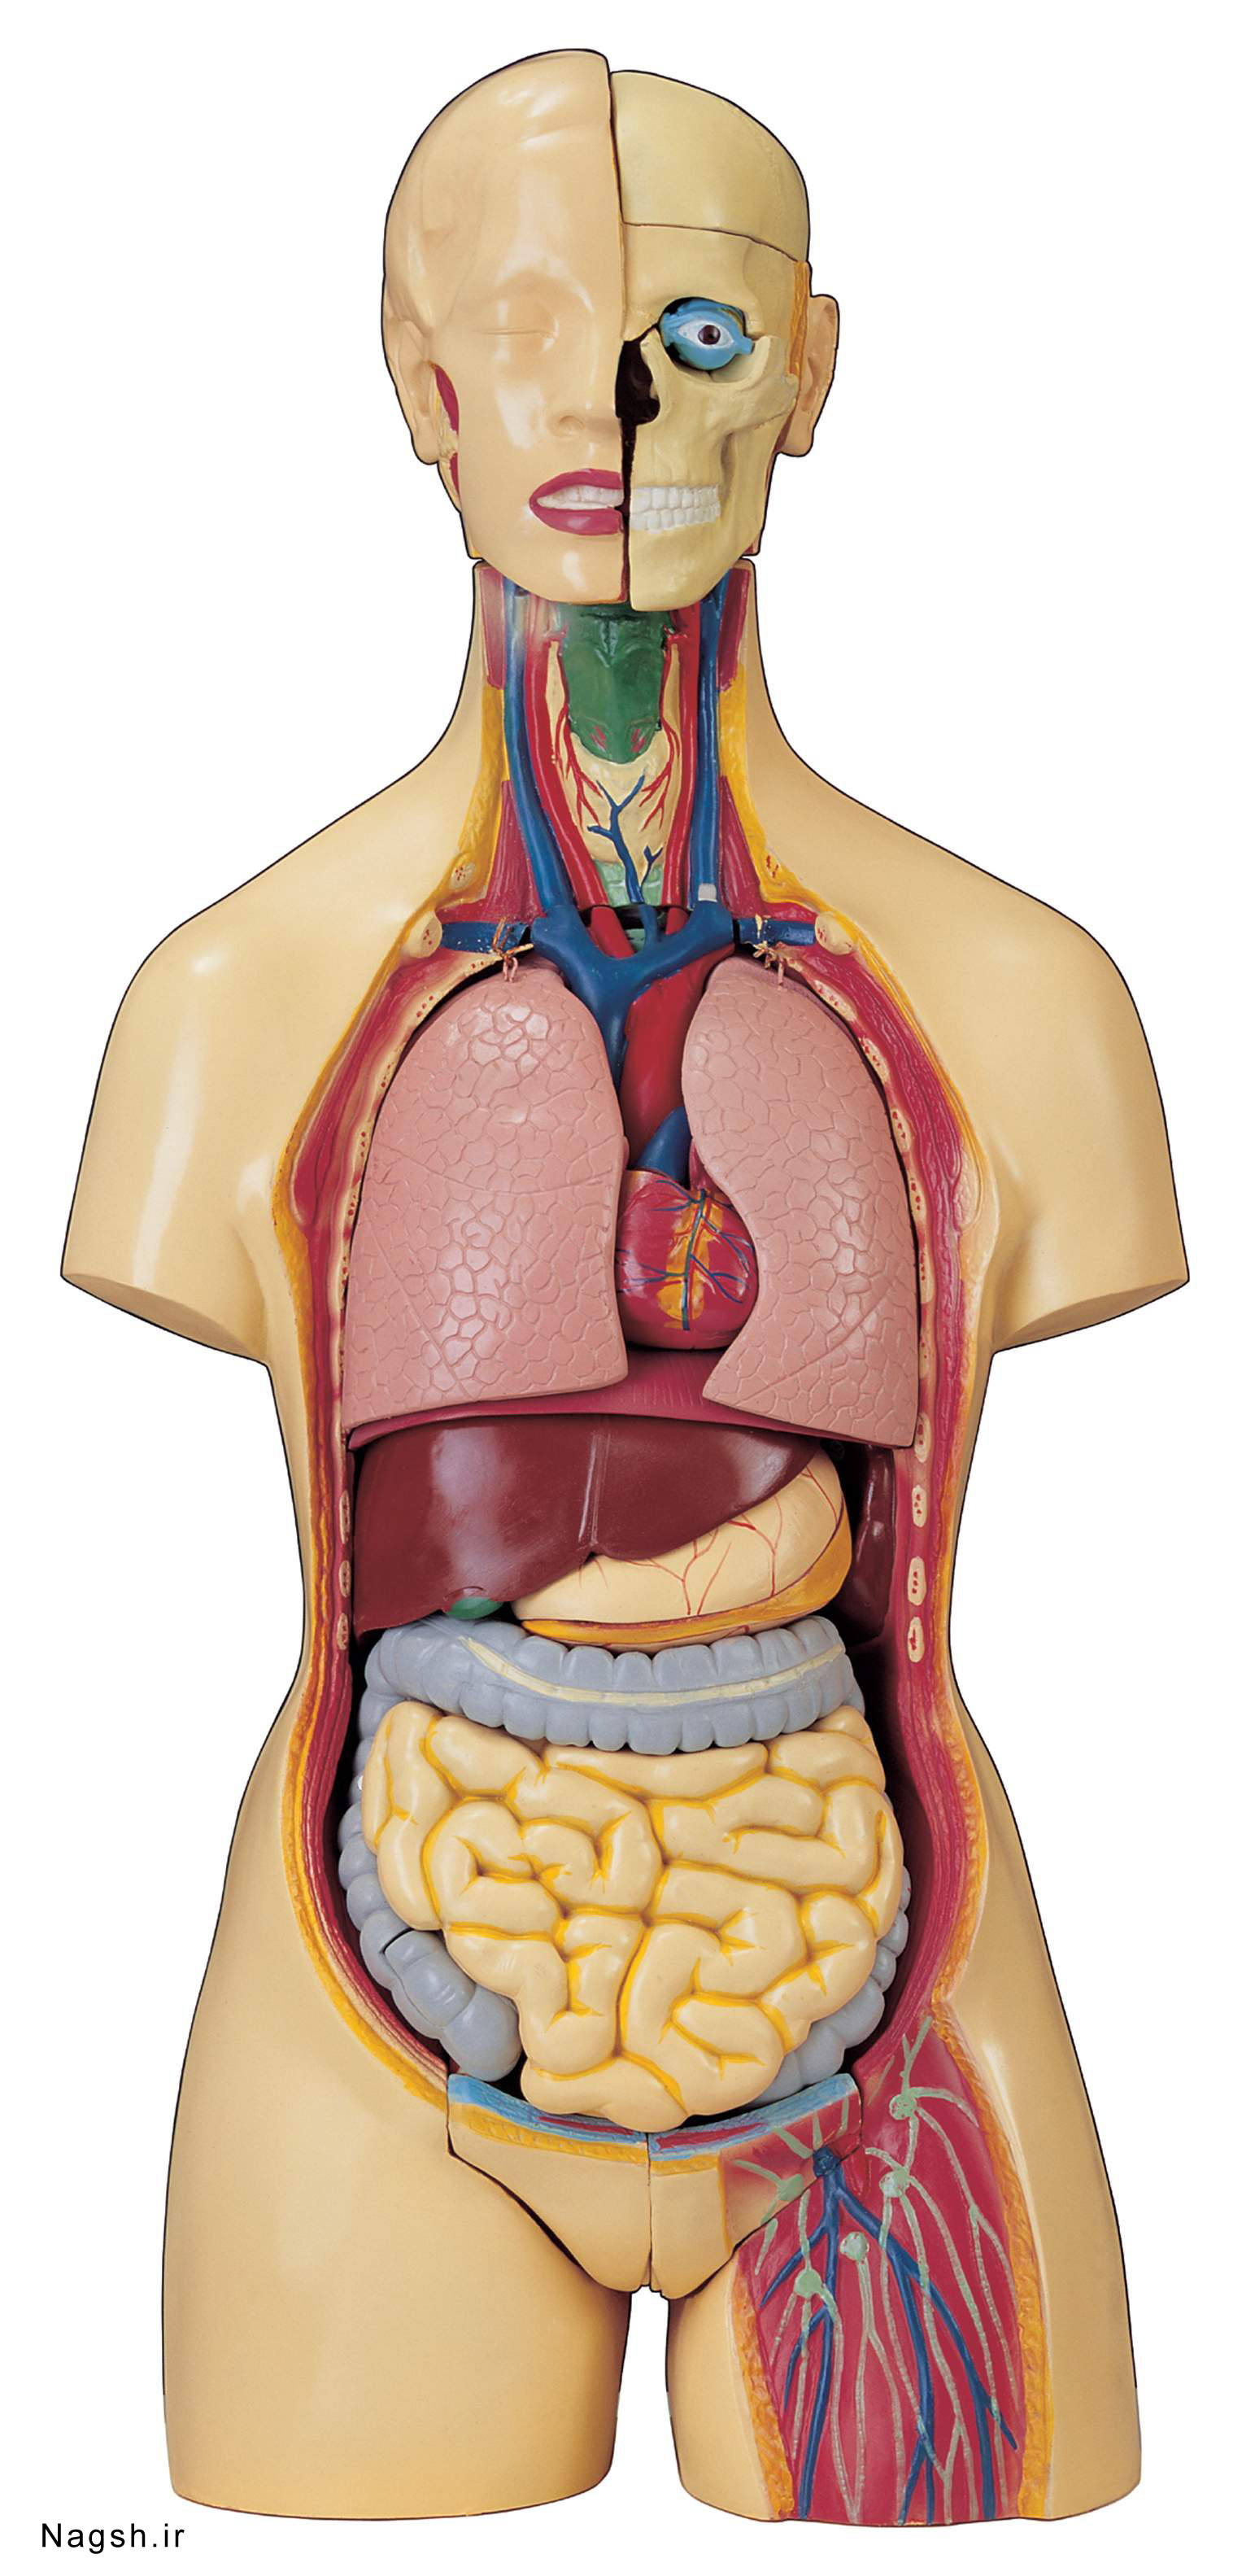

آناتومی سه بعدی بدن انسان عکس گرافی بدن.

اسکلت داربست بدن است تمام قسمت های بدن روی اسکلت قرارگرفته اند بدن انسان از ۲۰۶ قطعه استخوان تشکیل شده است این استخوان ها طوری با نظم کنار هم قرار گرفته اند که انسان را قادر می سازد حرکات دقیقی داشته باشد. استخوان یک نسج بسیار محکم است زیرا در ترکیب آن منرالها مانند کلسیم و دیگر وجود. اسکلت داربست بدن است تمام قسمت های بدن روی اسکلت قرارگرفته اند بدن انسان از ۲۰۶ قطعه استخوان تشکیل شده است این استخوان ها طوری با نظم کنار هم قرار گرفته اند که انسان را قادر می سازد حرکات دقیقی داشته باشد. آناتومی سه بعدی بدن انسان عکس گرافی بدن امعاء و احشاء بدن آناتومی سه بعدی بدن انسان عکس گرافی بدن امعاء و احشاء بدن قلب کبد روده.